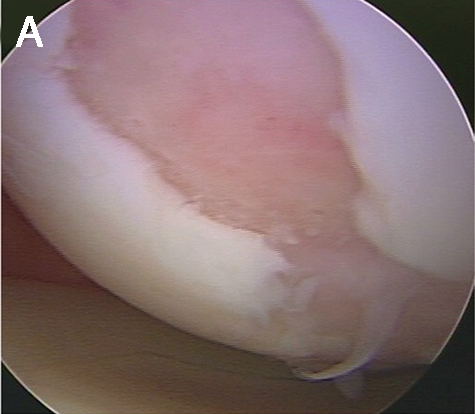

Diz ekleminde kıkırdak yaralanmasının artroskopik görüntüsü

Mikrokırık Yöntemi: Sınırlı ve 3 cm2’den küçük kıkırdak yaralanmasında uygulanan bir tedavi yöntemidir. Bu yöntemin avantajları tek bir ameliyat gerektirmesi ve artroskopi ile yapılmasıdır. Dezavantajı ise, oluşan tamir dokusunun kıkırdak benzeri olmasıdır. Yeni kıkırdak benzeri doku oluşana kadar, ameliyat sonrası altı-sekiz hafta eklem yüklenmeden korunmalıdır.

| A. Kıkırdak lezyonu ve B. Mikrokırık uygulaması | |